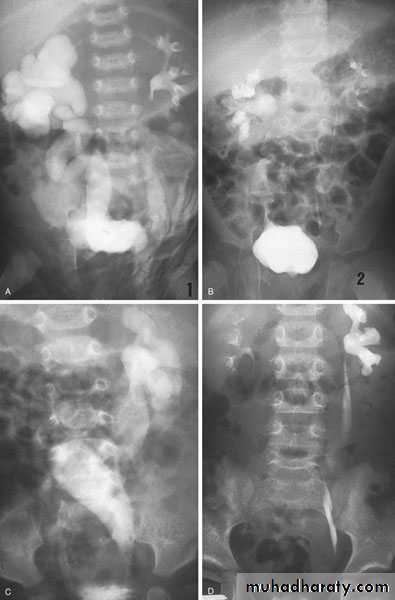

Horseshoe Kidney

found in 1:1000 necropsies an is commoner in men.

probably the most common of all renal fusion anomalies

The anomaly consists of two distinct renal masses lying

vertically on either side of the midline and connected at

their respective lower poles by a parenchymatous or fibrous

isthmus that crosses the midplane of the body.

Fusion of the renal masses early in embryonic life, so its ascent

will be impeded by inferior mesenteric artery.

The kidneys are low located, mal rotated and pelves lie anteriorly

Symptom When present, they are related to complications like hydronephrosis, infection, or calculus formation

Diagnosis ultrasound, IVU, CT scan